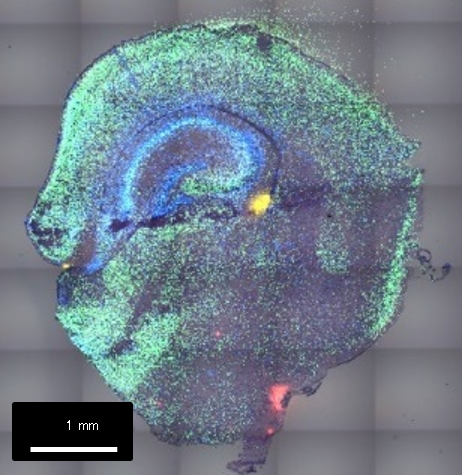

プロジェクション

遺伝子発現一覧 (組織特異性の高い順)

一部領域の拡大図 (下)

色付きのドット一つが1細胞相当/白点は細胞核

Tuba1a:滑脳症の原因遺伝子の一つ

空間解析結果をStereoMapというソフトウェアで可視化した結果をお示しします。部位特異性の高い遺伝子を一覧、それぞれの発現パターンを組織のイメージと重ね合わせて可視化することが可能です。

例えば、滑脳症の原因遺伝子とされているαチューブリンの遺伝子は主に皮質部分で発現、家族性アミロイドポリニューロパチー (FAP) への関連が示唆されているトランスサイレチン遺伝子は、海馬付近で特異的に発現していることが観察できます。